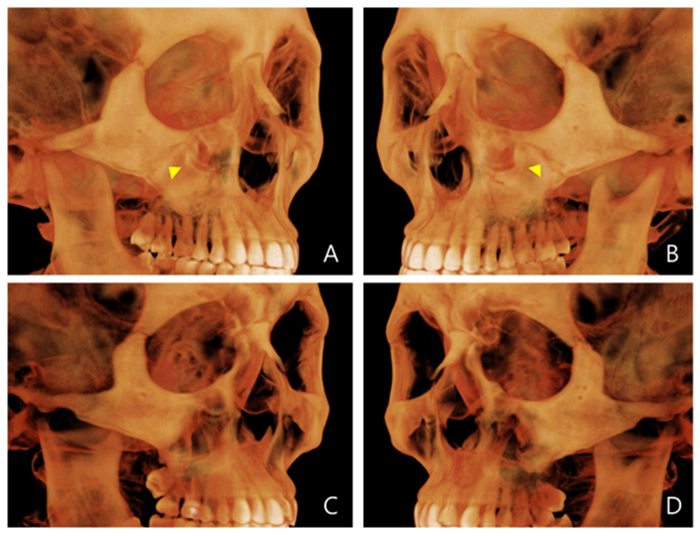

확장 전

확장 전

확장 후

확장 후

확장 전

확장 전

확장 후

확장 후

이지민 원장은 성인 비발치 교정의 핵심인 비수술 악궁 확장 가능성을, 직접 연구한 논문 결과를 바탕으로 사전에 정밀 분석·예측합니다.